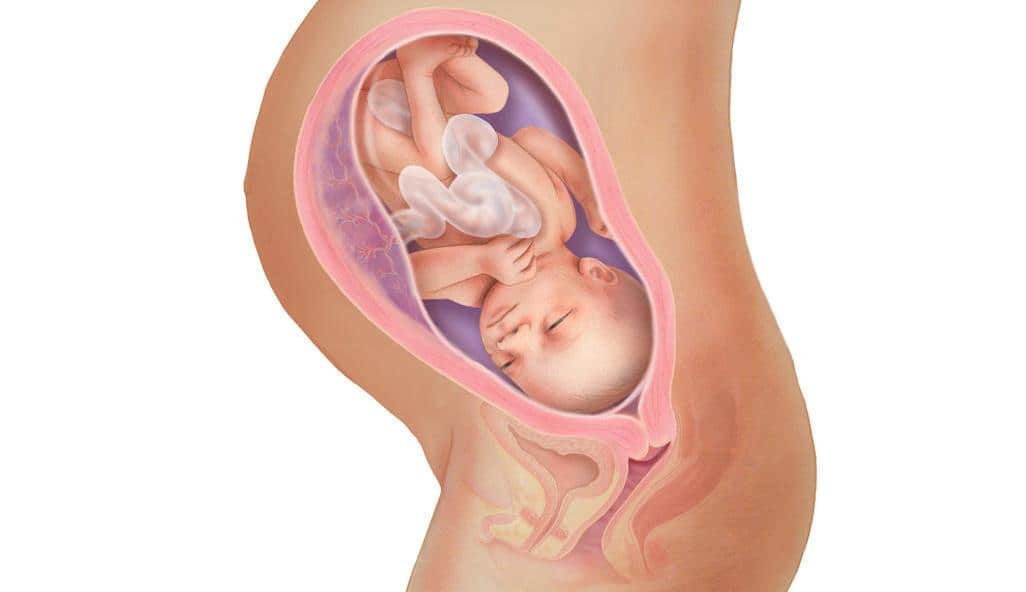

Тошнота на 37 неделе беременности: причины и рекомендации